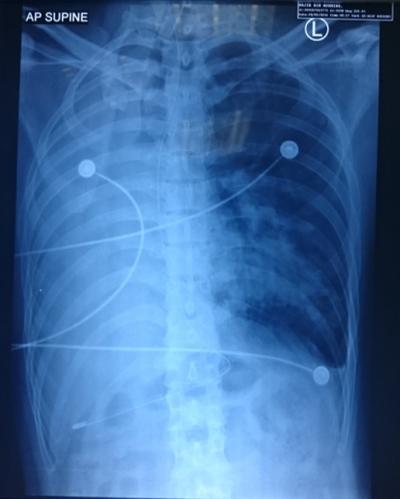

Foreign Body Aspiration in Adult

bronchoscope

emergency department

fibre optic

Foreign body aspiration

Case report